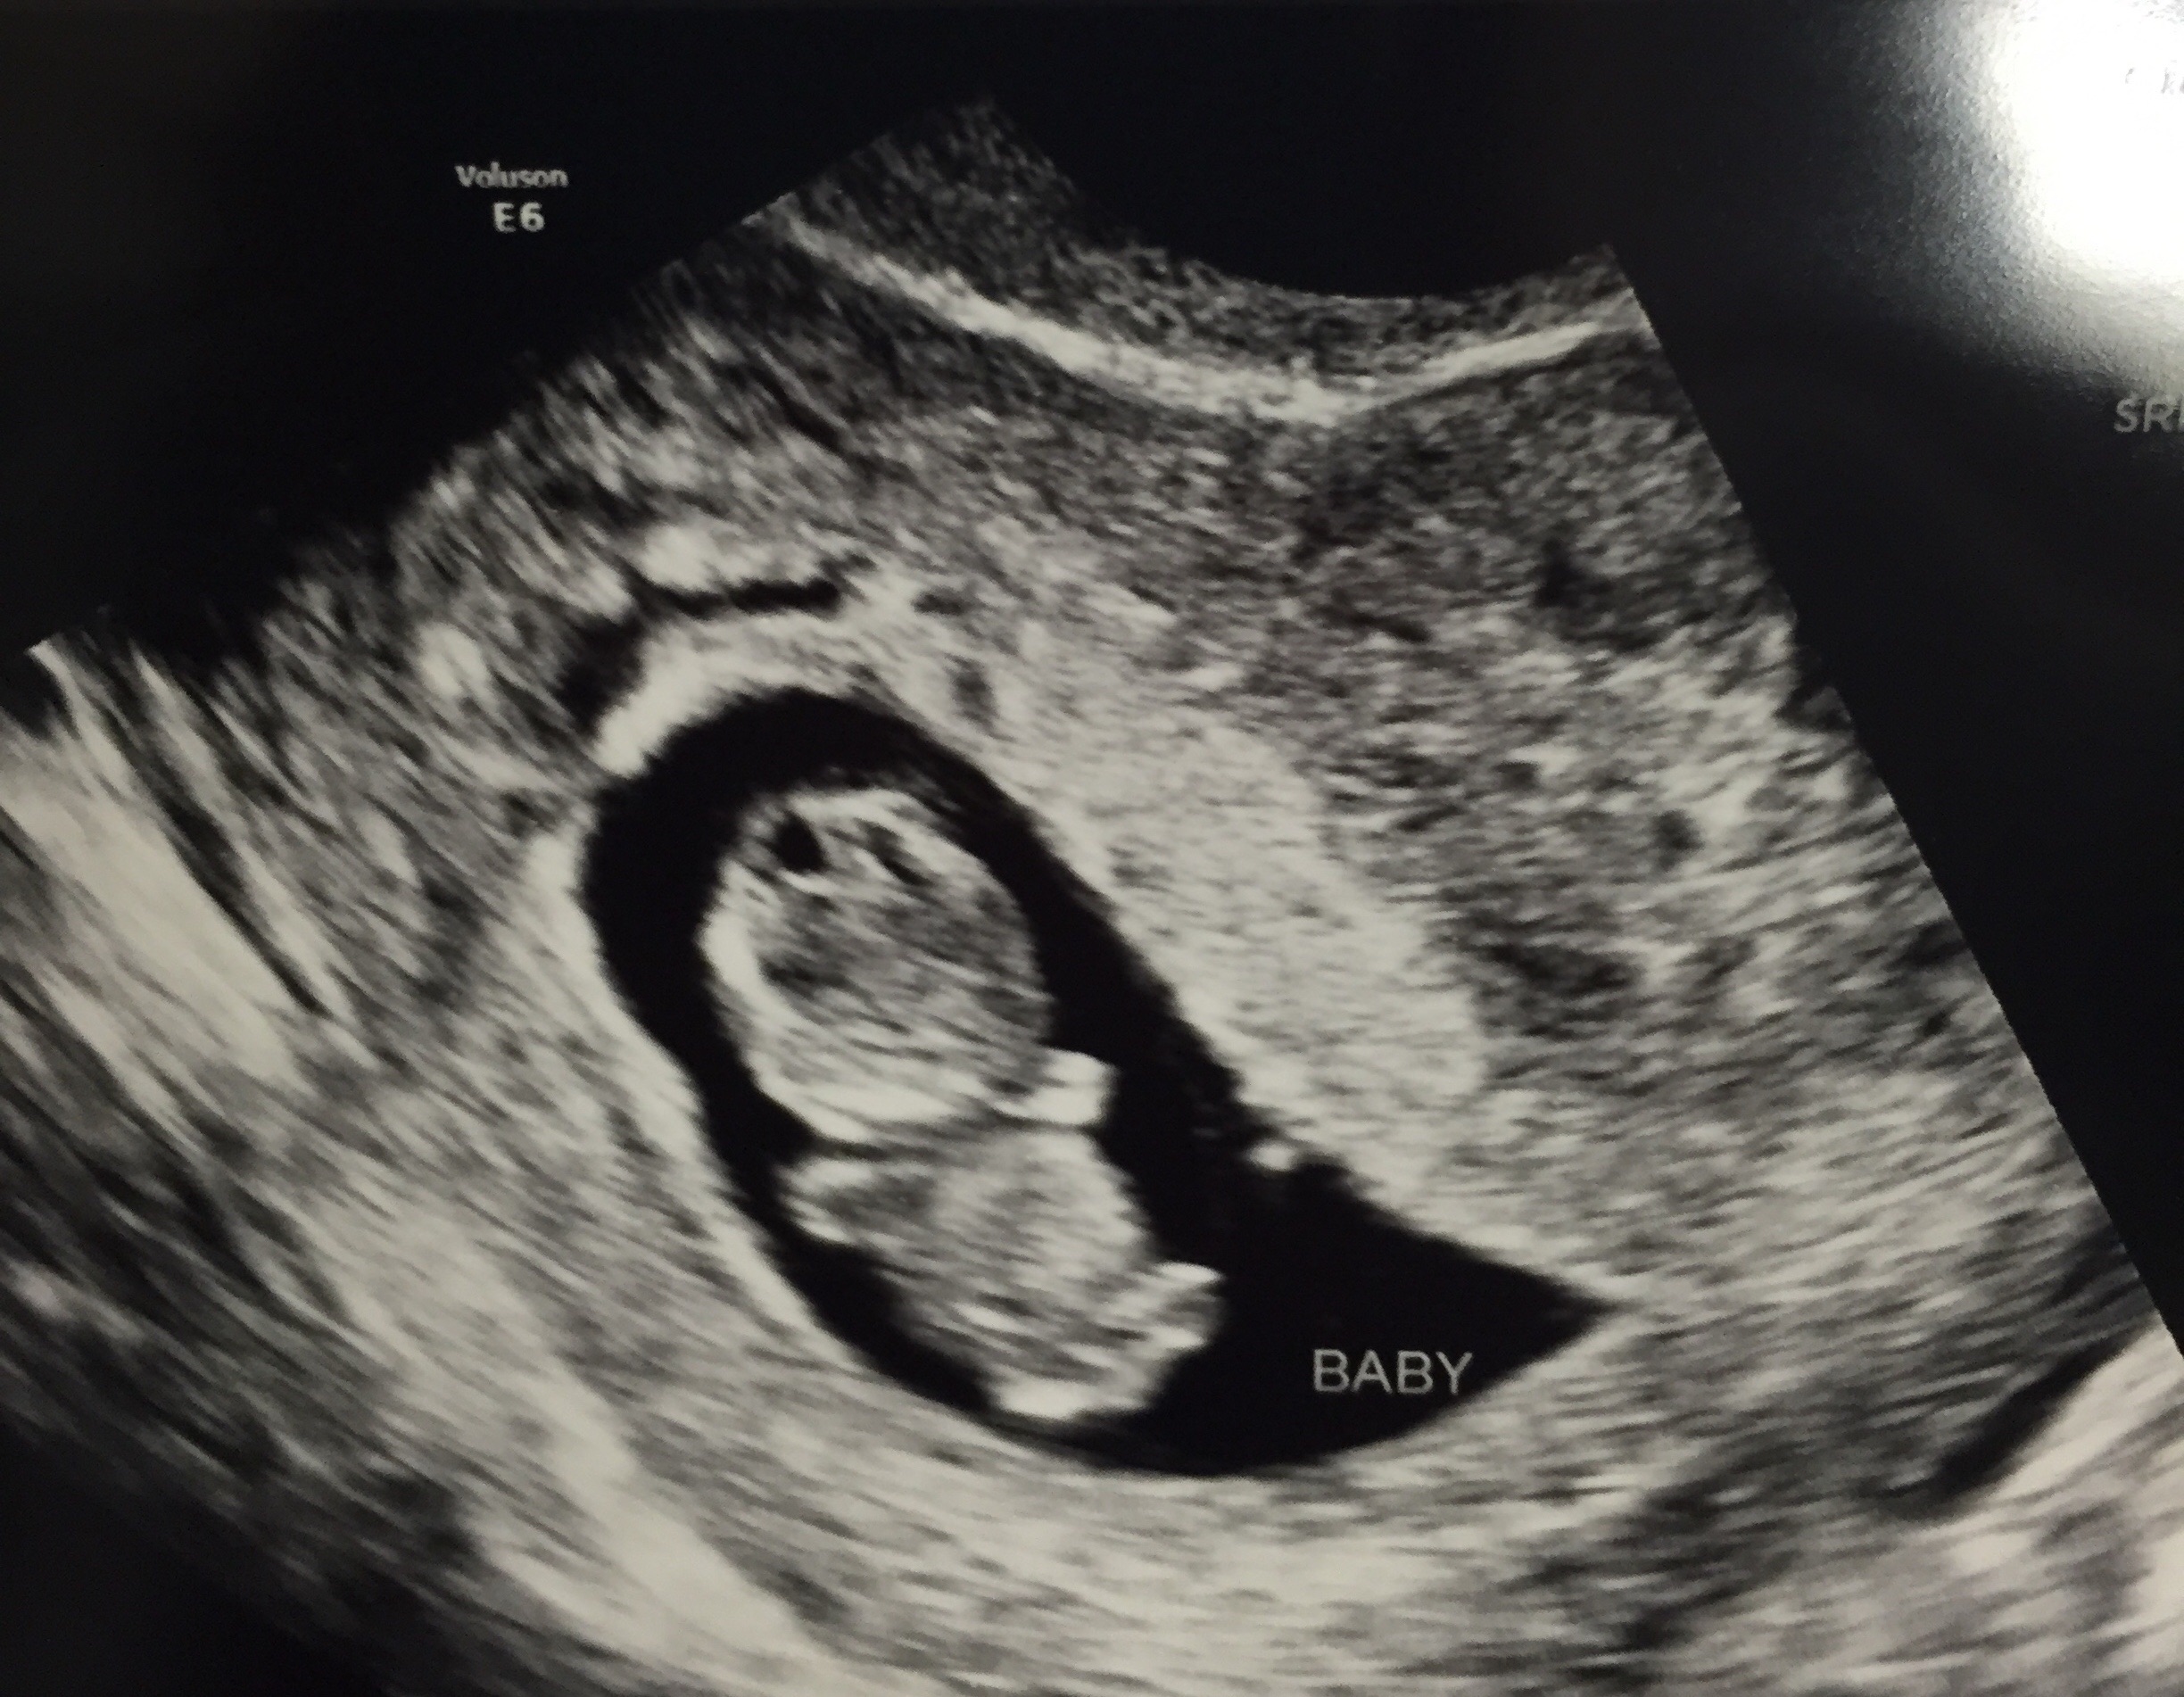

Oh I'm so excited to post! Had a mini scare over the weekend and went in for a super quick scan yesterday to make sure everything was ok! It was Great actually! Heard the little ones heartbeat for the 1st time - AMAZING. Here (s)he is at 10 weeks 6 days.